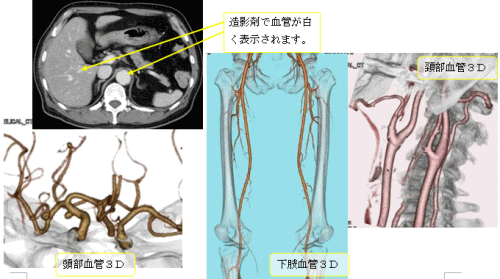

造影剤という薬を注射してから撮影を行います。撮影する部位や方法の違いで、何回か撮影することがあります。また、血管の3D撮影も行います。通常は、単純CTを撮影したあと造影剤を注射して造影CTを行いますが、造影CTのみの場合もあります。

造影剤が入ると血管や腫瘍などがはっきりと写るようになります。

○で囲まれたところに単純画像ではわかりませんが、造影剤が入ると白く映ります。